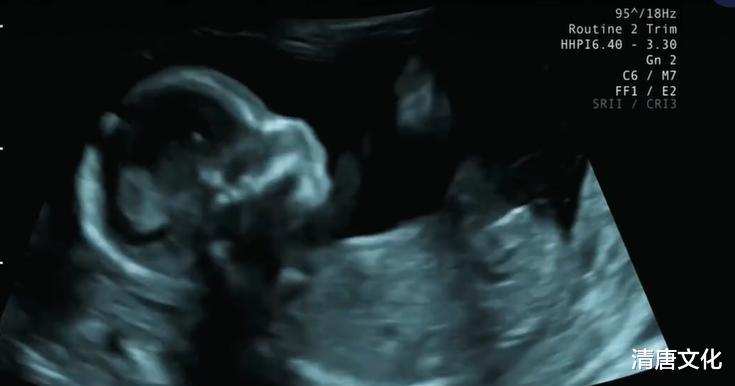

程晓玥的个性比较独立,但并不是很强势的性格,主要自身家境条件的关系,可能在花钱方面确实比较奢侈吧,另外孩子的B超照片曝光,看起来很健康,而且在妈妈肚子里面很活跃,早前感觉程晓玥的长相有点寡淡,但自从怀孕后整个人变得柔和,感觉会生个男孩子。